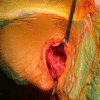

Osteochondromas commonly affect the proximal humerus, pelvis, and knee but are rarely seen on flat bones. Herein, we present the case of a 15-year-old female patient with osteochondroma located at the dorsal aspect of the scapula. The patient was admitted to the Orthopedics and Traumatology Department with the complaint of a mass on the left upper back for five years. The patient complained of the inability to sleep in the supine position, pain with shoulder motion, and cosmetic discomfort for two years. X-rays of the left shoulder revealed a bony mass arising from the dorsal aspect of the left scapula. The patient underwent an operation, and a specimen was sent for histopathologic examination. The histopathologic investigation confirmed the diagnosis of non-malignant transformation osteochondroma. While osteochondroma is not common in the scapula, it should be kept in mind that the most common benign tumor of the scapula is osteochondroma.